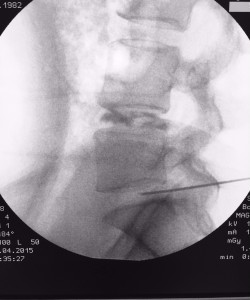

Infiltração na

Coluna

Infiltração na Coluna

As infiltrações na coluna costumam trazer alívio imediato da dor e melhora da movimentação da coluna de forma definitiva ou temporária e, ainda por cima, ajudam o cirurgião a identificar a estrutura exata responsável causadora da dor.